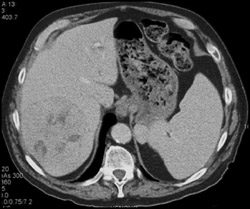

Prior Hepatic Infarction